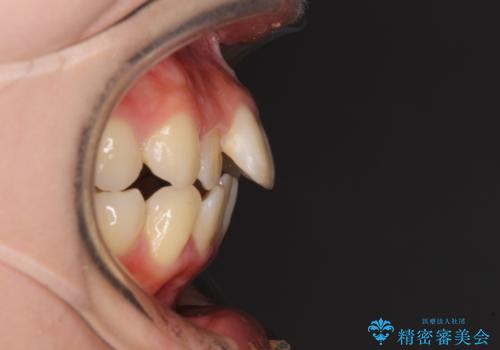

上下ともに歯列が前方に突出していたため、上下左右の第一小臼歯4本を抜去し、ワイヤー装置による矯正治療を行うこととしました。

上下左右4本抜歯する場合には、通常2年から2年半ほどの期間を要しますが、僅か1年半で終了することができました。